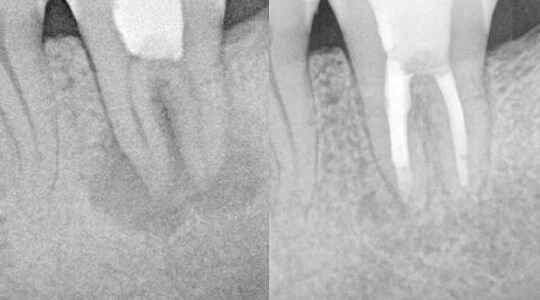

Nach vollständiger Instrumentation und Desinfektion des Wurzelkanalsystems muss das entstandene Hohlraumsystem mit einem Füllmaterial bakteriendicht versiegelt werden. Optimale Ergebnisse lassen sich mit der sogenannten dreidimensionalen thermoplastischen Obturation erreichen: Eine Art Gummi wird in erwärmten, fließfähigem Zustand in die Kanäle eingebracht und durch nachfolgender Kompression in die Hohlräume hineingepresst. Anschließend wird der Zahn mit einem stabilen Aufbau fest verschlossen (Bild links). Dieser dient auch als Vorbereitung für eine spätere eventuell notwendige Überkronung (Bild rechts). In den folgenden Monaten heilt die Entzündung um die Wurzelspitzen des jeweiligen Zahnes ab, der zuvor geschwundene Knochen regeneriert sich wieder (Fallbeispiel im nächsten Abschnitt)

Bild links: Sehr große Entzündung an einem unteren Backenzahn mit durch die Entzündung kompliziert „angelösten“ Wurzelspitzen.

Bild rechts: Nach speziellem Einsatz von „Reparaturzement“ und abschließender Desinfektion und Auffüllen des Wurzelkanalsystems abgeklungene Entzündung mit einhergehender Regeneration des Knochens.